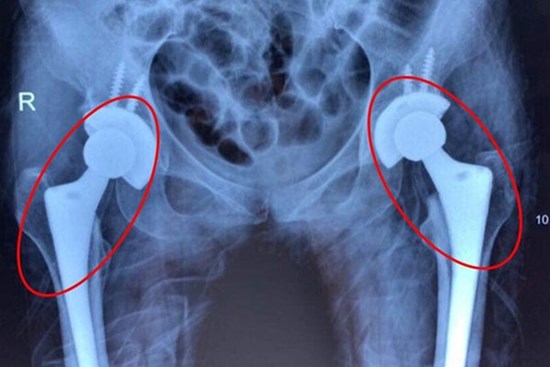

Nhiều người trẻ bị mục xương vì chất kích thích ai cũng dùng

Tắc mạch máu diễn tiến âm thầm khiến nhiều bệnh nhân bị mục cả 2 khớp háng, đối mặt nguy cơ tàn phế. Bác sĩ cảnh báo, nguyên nhân dẫn tới tình trạng trên là do người bệnh lạm dụng rượu bia. Giải pháp để cứu bệnh nhân là thay cả 2 khớp háng.